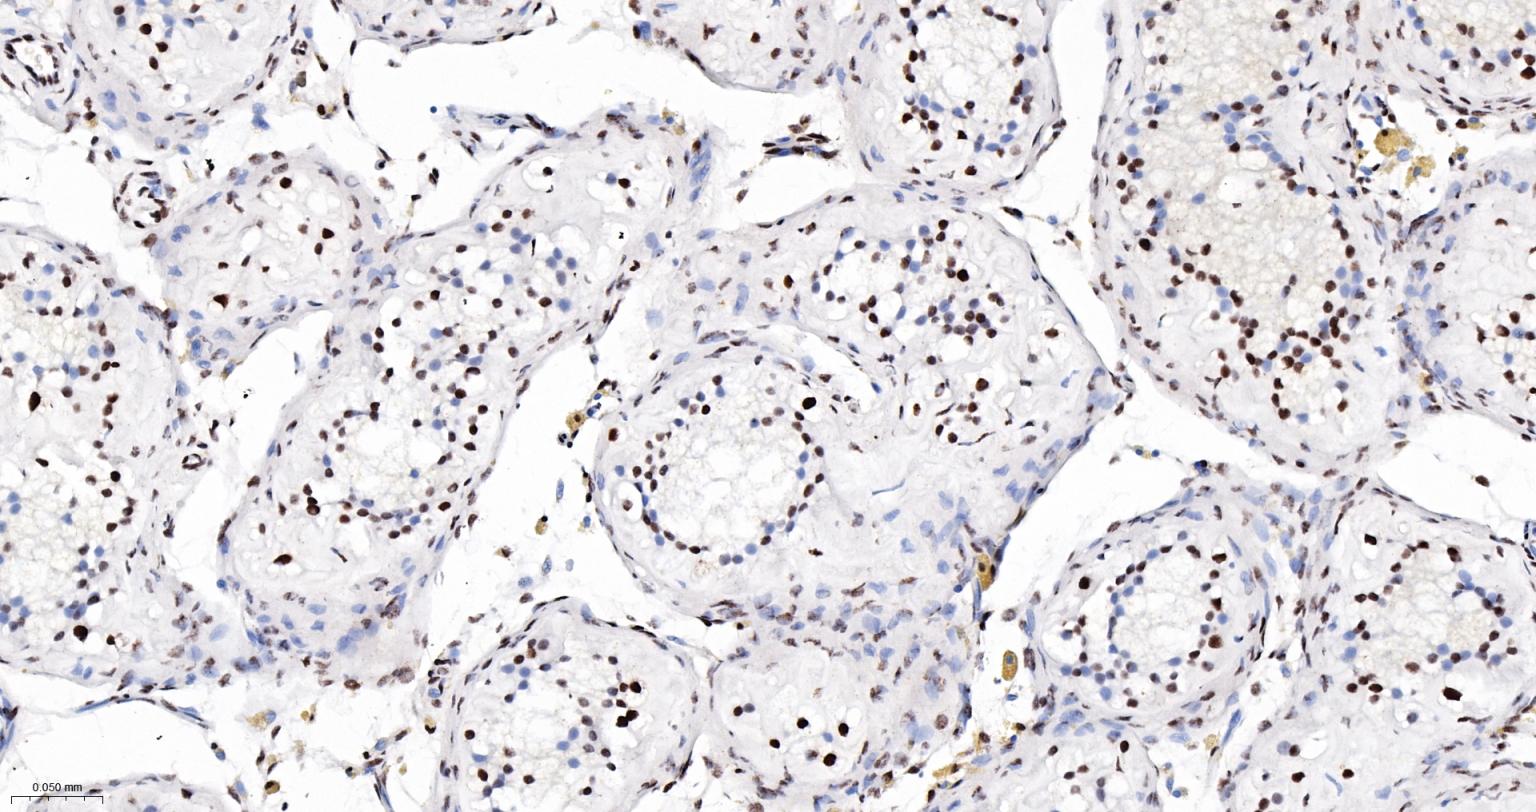

Paraformaldehyde-fixed, paraffin embedded Rat Testicles; Antigen retrieval by boiling in sodium citrate buffer (pH6.0) for 15 min; The section was incubated with DDX9 Monoclonal Antibody, Unconjugated (bsm-61787R) at 1:200 overnight at 4°C, followed by conjugation to the bs-0295G-HRP and DAB (C-0010) staining.